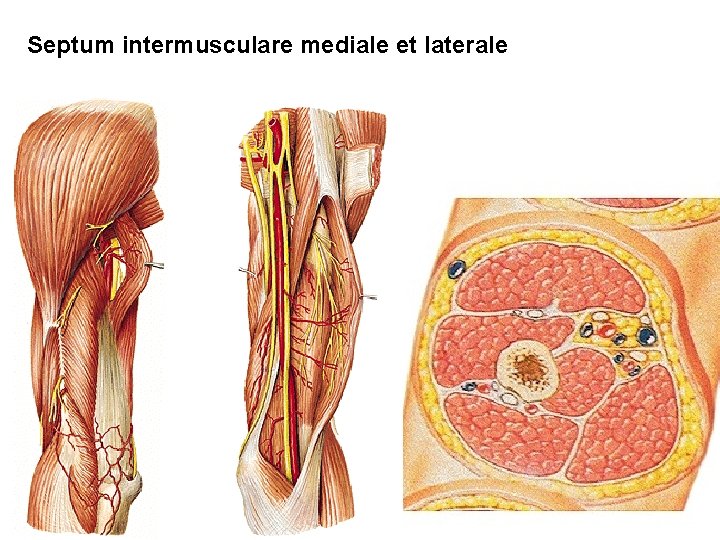

Septum intermusculare mediale et laterale

Anterior group of muscles: M. biceps brachii caput longum caput breve aponeurosis m. bicipitis brachii M. coracobrachialis M. brachialis N. musculocutaneus

A. BRACHIALIS - a. profunda brachii - a. collateralis ulnaris sup. - a. collateralis ulnaris inf. - a. radialis - a. ulnaris

Sulcus bicipitalis medialis - a. brachialis - vv. brachiales - n. medianus - v. basilica - n. cutaneus antebrachii med. - a. collateralis ulnaris sup. - vv. coll. ulnares sup. - n. ulnaris N. musculocutaneus N. radialis A. coll. media V. profunda brachii

CROSS SECTION THROUGH THE ARM N. cutaneus antebrachii med. N. musculocutaneus N. medianus N. radialis N. ulnaris